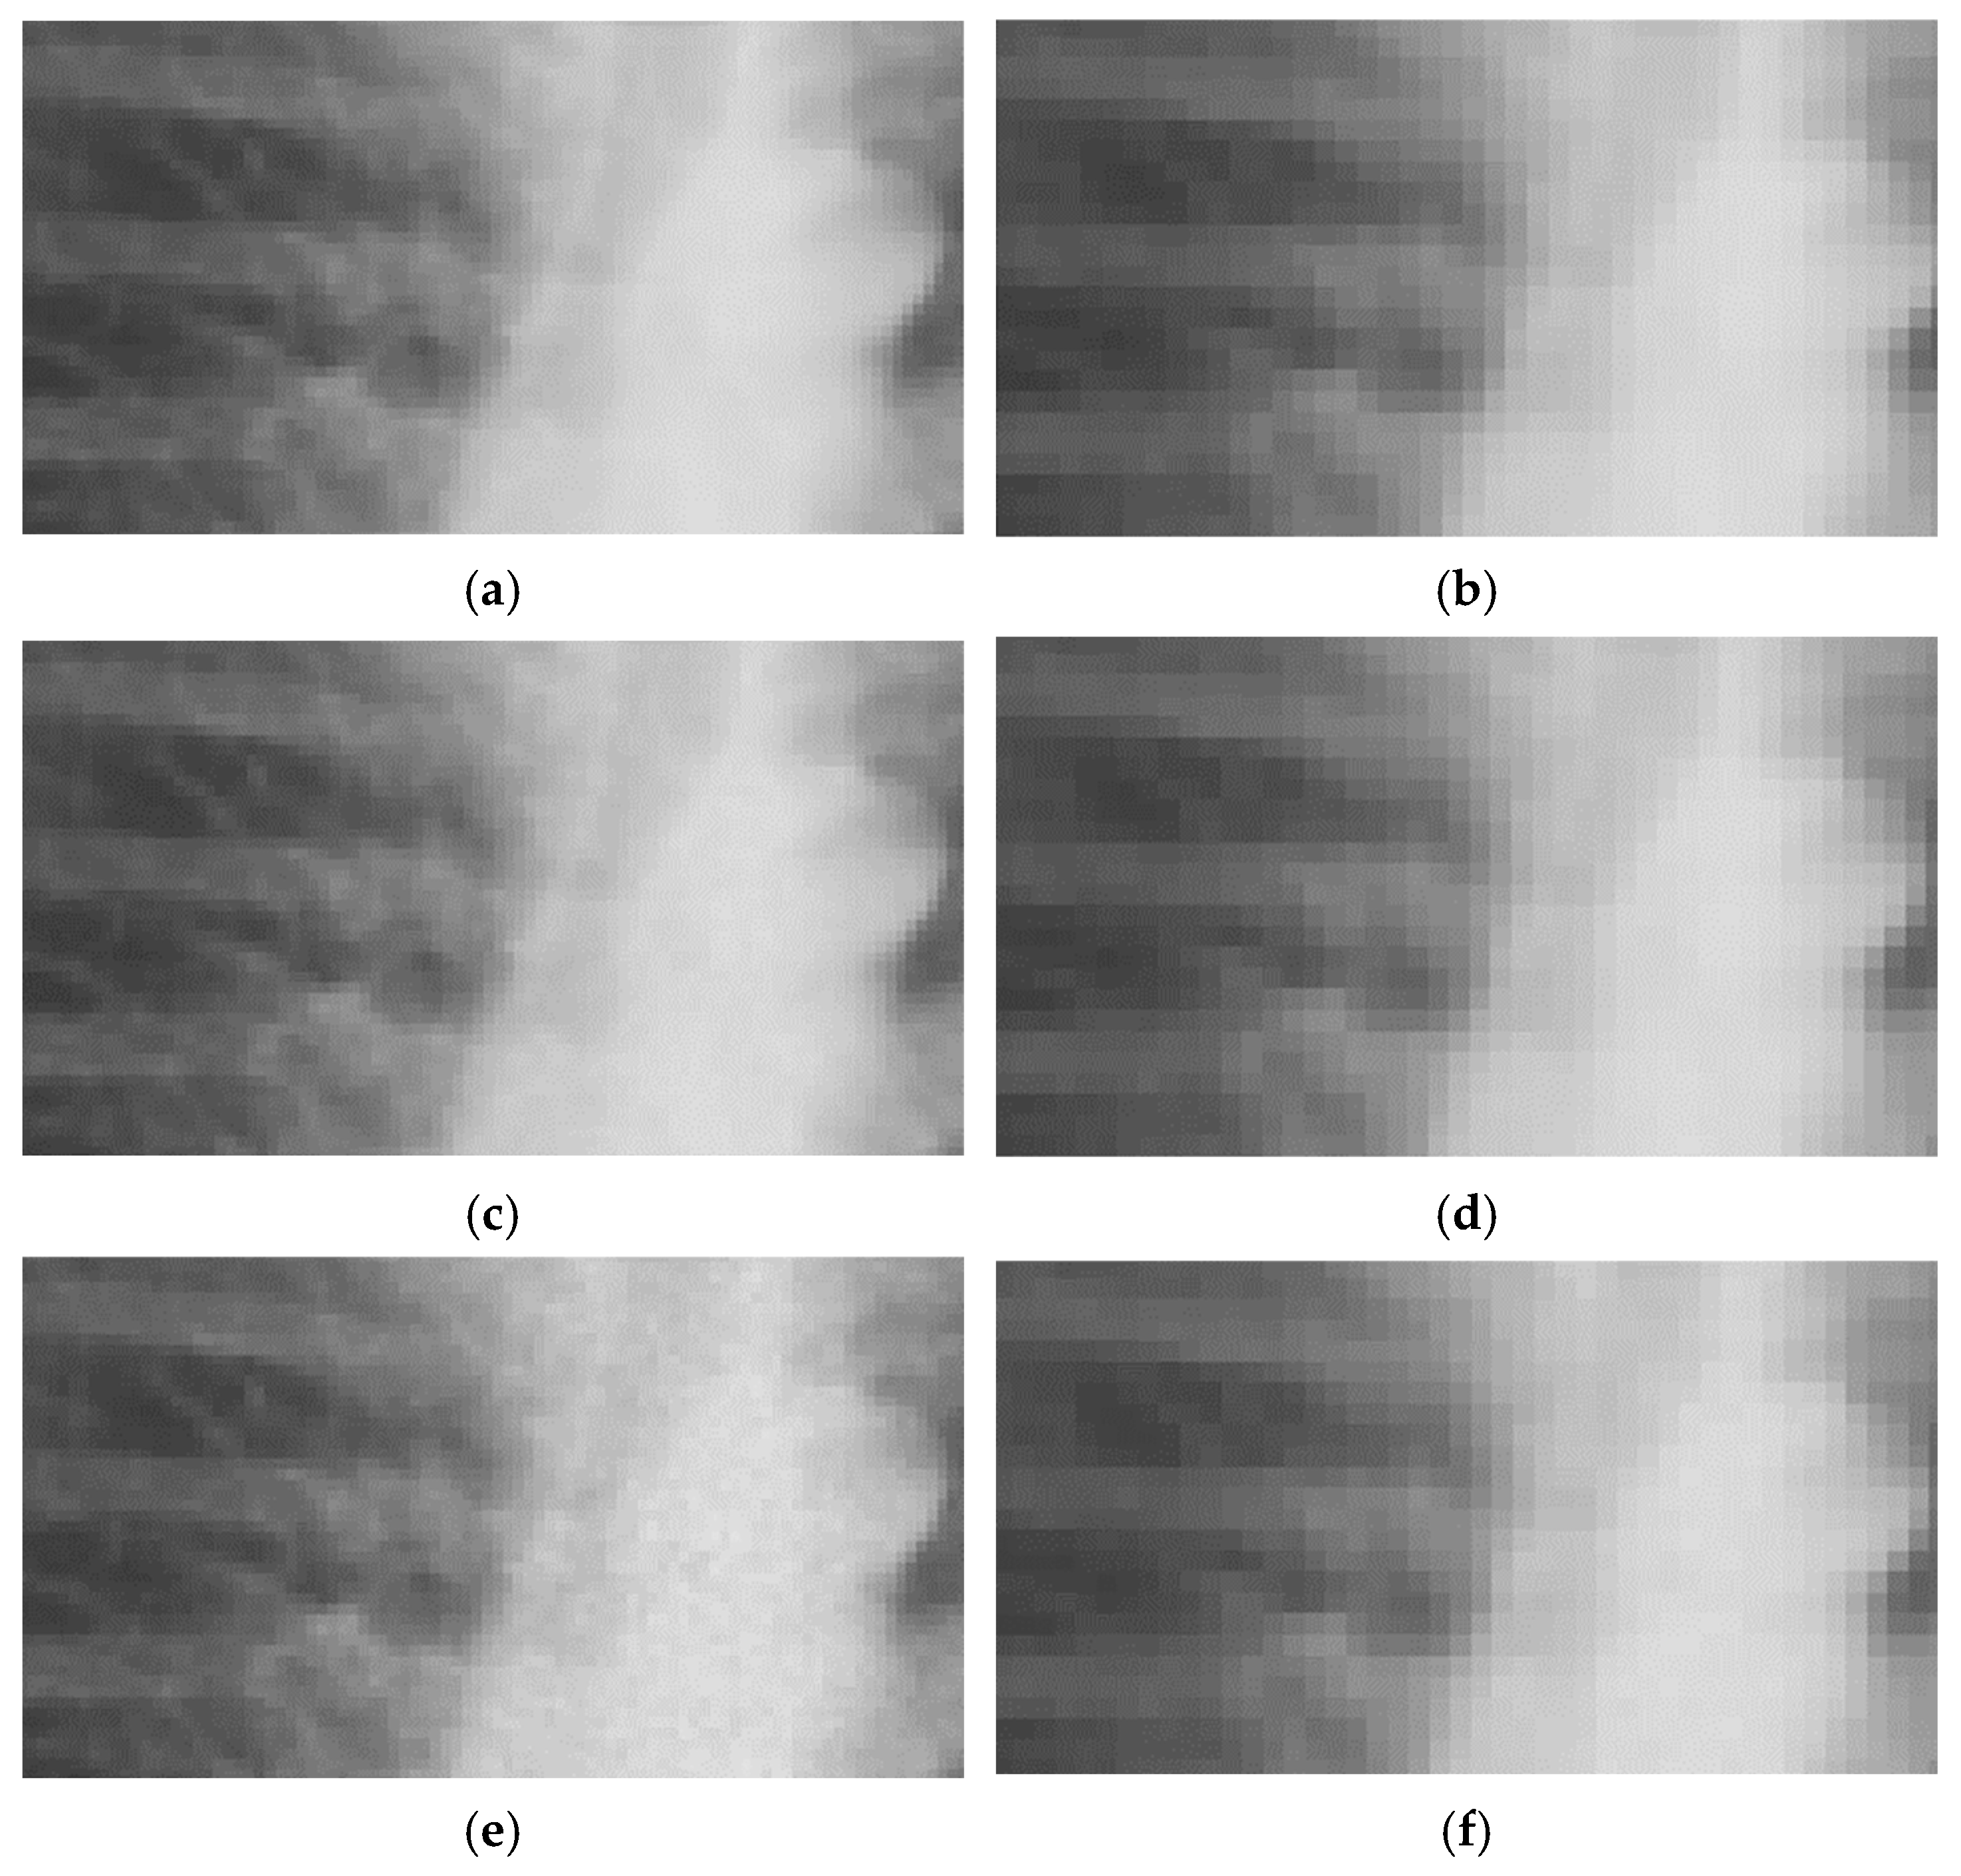

After lowering images resolution to LR and ULR used for CNN input, the noise generated by InGen is less prominent compared to the original full-resolution images, as shown in Figure 3. Note the difference in expression of noise in the examples shown in Figure 2 and Figure 3. SSIM shows comparable results as the full resolution images with all values > 0.998. This indicates a smaller impact of noise on structural similarity. PSNR measurements were higher for lower resolutions, as shown in Table 3, which also indicates a smaller effect of noise on lower resolutions.

Figure 3. Representative examples of MIMIC-CXR images with different noise levels on training and testing resolutions. LR ((ac): 254 × 305 px), ULR ((df): 127 × 152 px), and normal exposure (a,d); 50% (b,e) and 75% (c,f) simulated dose reductions.